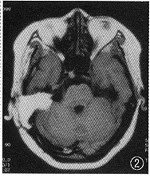

图2 例1患者术后2月MRI示肿瘤全切,术后面肌功能1级

图4 例5患者术后2月MRI示肿瘤全切,术后面肌功能2级

本组病例肿瘤均全切除,无手术死亡,未发生颅内感染及脑脊液漏。手术平均时间8 h,术中出血量平均为450 ml,其中2例给予输血。术中面神经保存4例,术后面肌功能1级、3级各1例,2级2例。另1例患者术前面瘫5级已1.5年,术中面神经中断,术毕即行面舌下神经吻合术。术后均已随访6个月以上。MRI复查均显示无肿瘤残存,脑组织无明显术后反应及损伤,脑干位置恢复正常,4脑室通畅(图1~4)。术后面部麻木均有改善或恢复正常。4例患者术后10~14 d步行出院,术后1~3个月恢复正常工作。1例神经纤维瘤病II型患者,术后1个月因顶叶巨大脑膜瘤周围水肿,转入脑外科行脑膜瘤切除术,术后康复顺利。